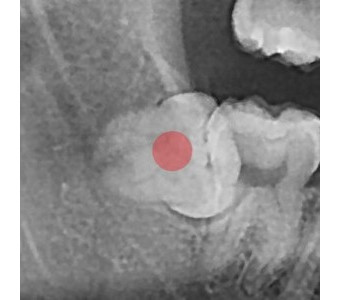

以成果证明实力。

国际摩牙齿科

真实临床案例